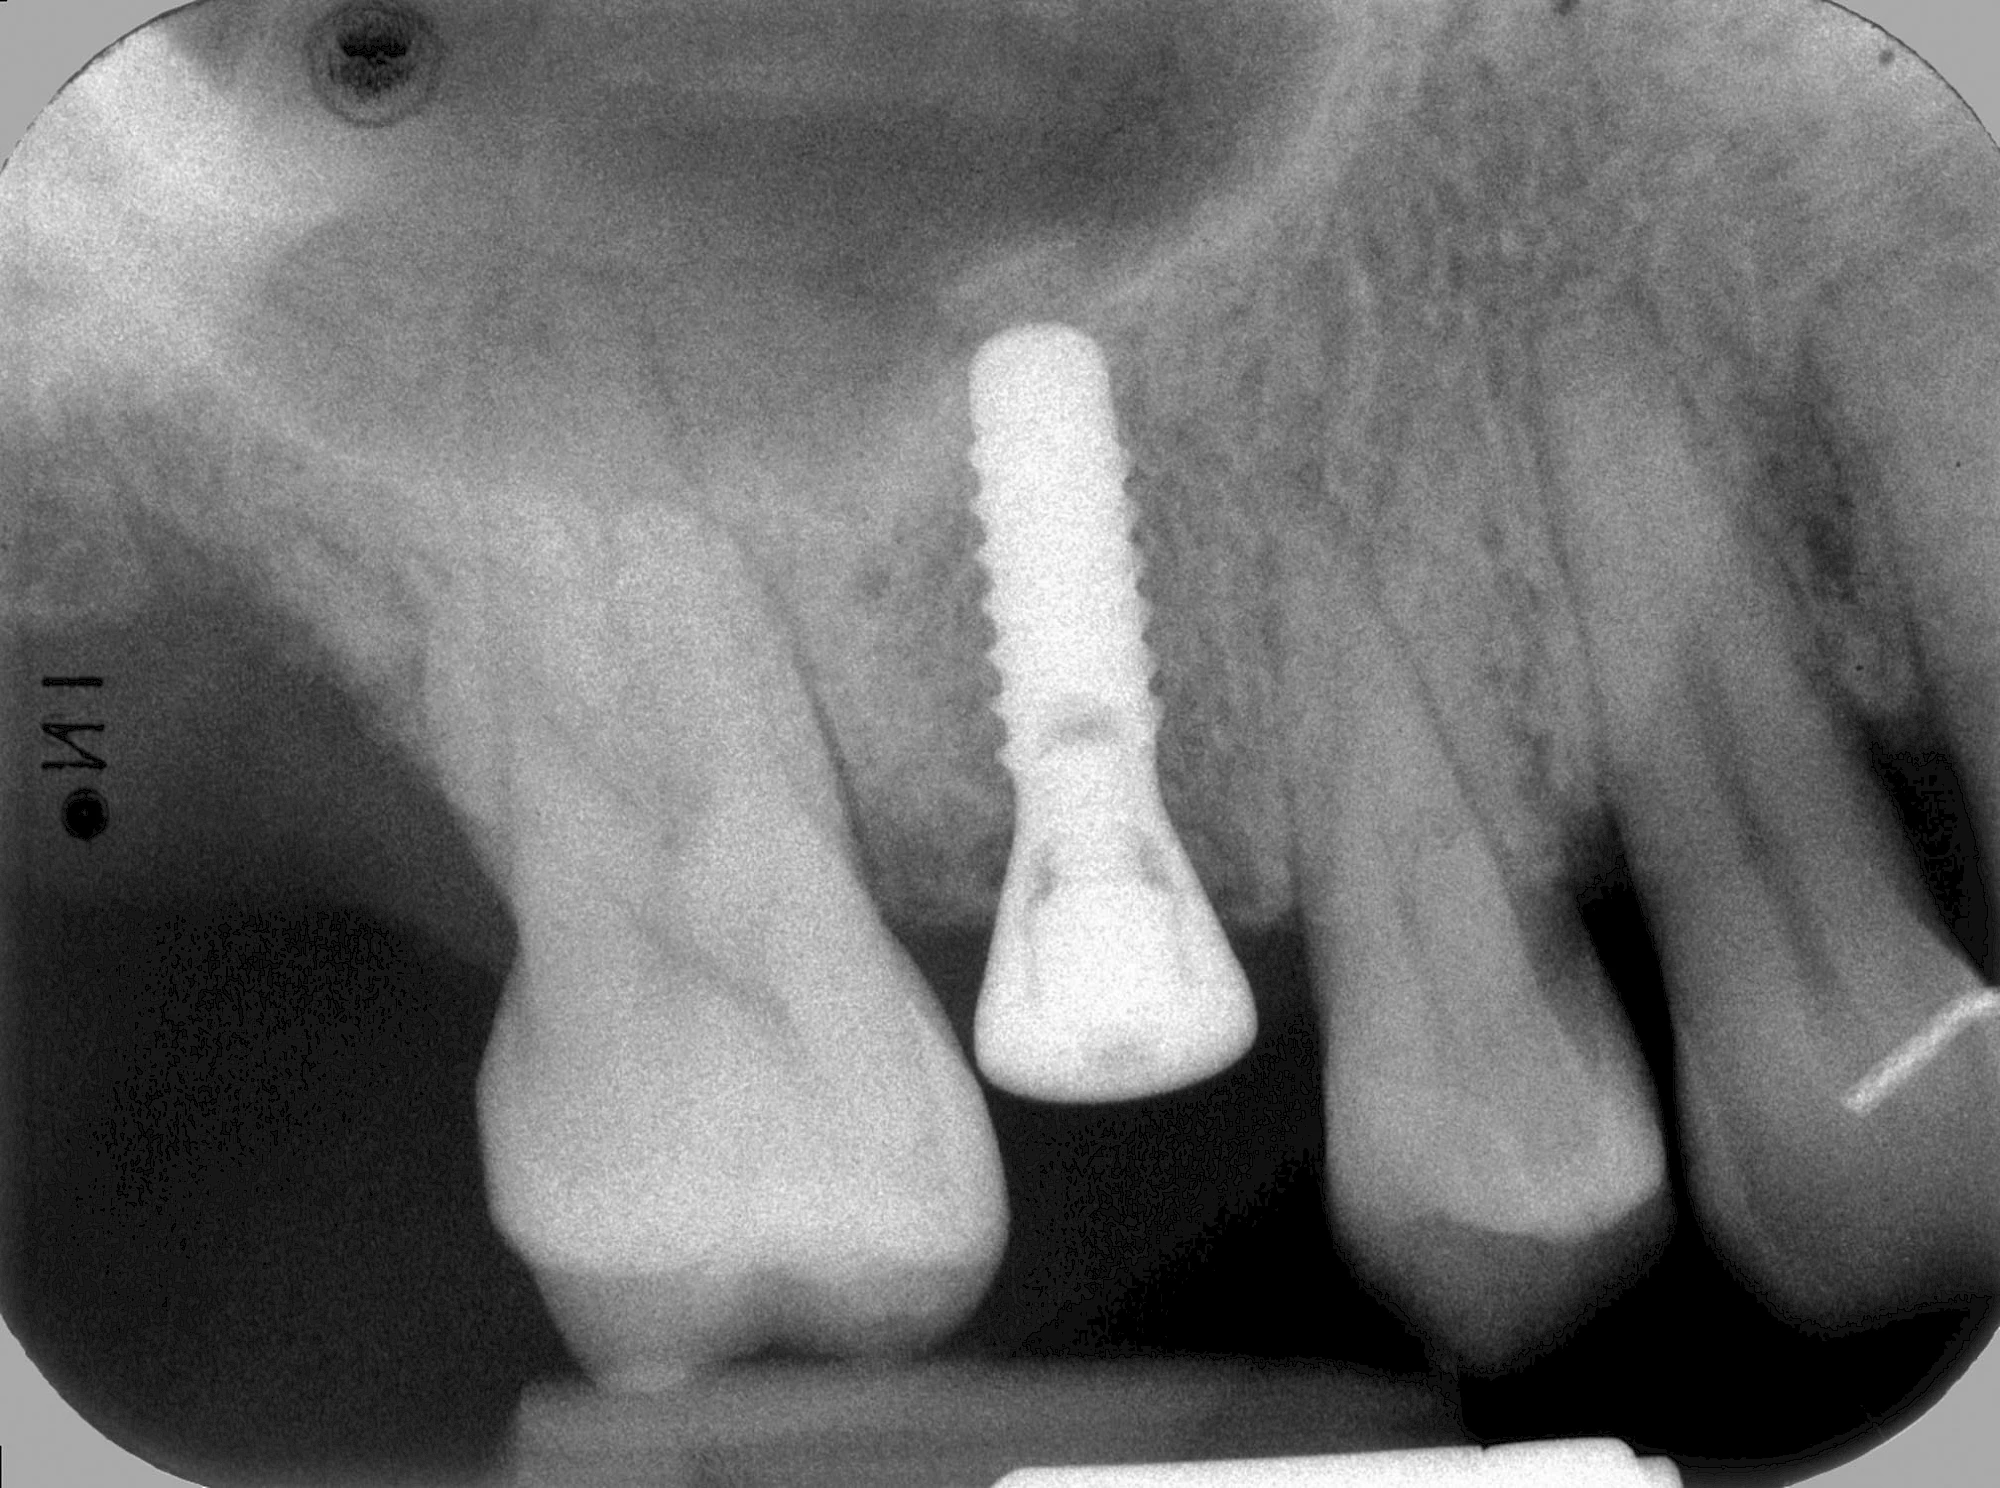

Implantate: Bestandteile

Implantate sind künstliche Zahnwurzeln. Nach einer gewissen Einheilzeit im Knochen (meist 3-6 Monate) erfolgt über einen separaten Aufbau (Abutment) die Befestigung einer Krone bzw. Brücke oder Zahnprothese.

Implantate haben im Gegensatz zu den eigenen Zähnen keine natürliche Abwehr und müssen deshalb besonders sorgfältig gepflegt werden.

Meist kommen als Materialien für Zahnimplantate Titanlegierungen oder zunehmend auch keramische Werkstoffe zum Einsatz.

In seltenen Fällen sind Implantate samt Aufbau aus einem Stück gefertigt. Auch gibt es Situationen, die ein Früh- oder sogar eine Sofortbelastung erlauben – dann kann die Einheilzeit der Implantate in den Knochen verkürzt oder sogar gänzlich darauf verzichtet werden.

"Stiftzahn" und "Implantat" ist nicht dasselbe! Bei einem Stiftzahn wird die Zahnkrone mit einem Stift in die noch vorhandene eigene Zahnwurzel zementiert. Ein Implantat im Gegensatz dazu ist selbst die (künstliche) Zahnwurzel, die dann weiter mit einem Zahnersatz versorgt wird.